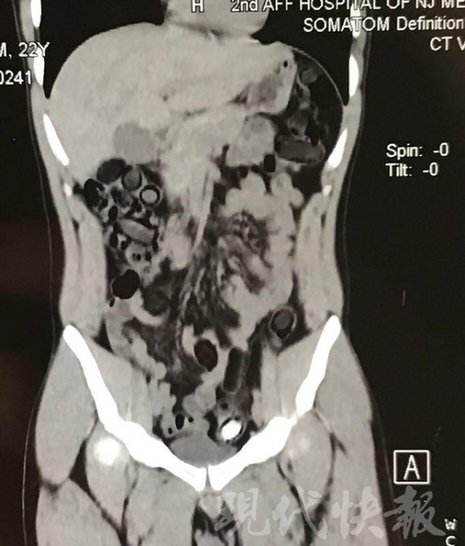

小伙體內(nèi)藏毒300余克 CT掃描圖密密麻麻

運(yùn)毒小伙:希望被判處死刑

由于毒品在體內(nèi)一旦泄露有可能致命,警方第一時(shí)間將阿永帶到醫(yī)院進(jìn)行檢查。CT 掃描的結(jié)果顯示,阿永體內(nèi)布滿了密密麻麻的白色圓柱狀固體,就像一粒粒的蠶蛹。在南京市公安局鼓樓分局二板橋派出所,阿永分四次排出了毒品,毛重369.99克。經(jīng)訊問,阿永交代了自己全部的犯罪事實(shí)。目前,阿永已被刑事拘留。